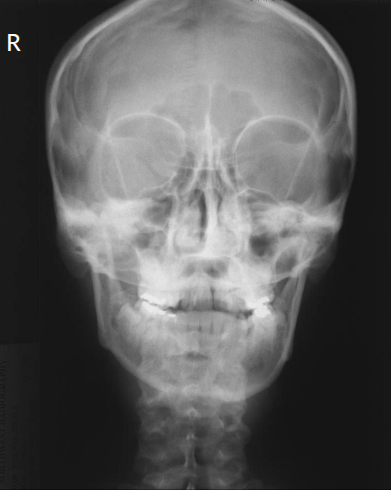

Q

what is the issue here

A

way too much angle

what is the correction

20-25 deg more caudad

lift chin to change OML by 20-25 deg